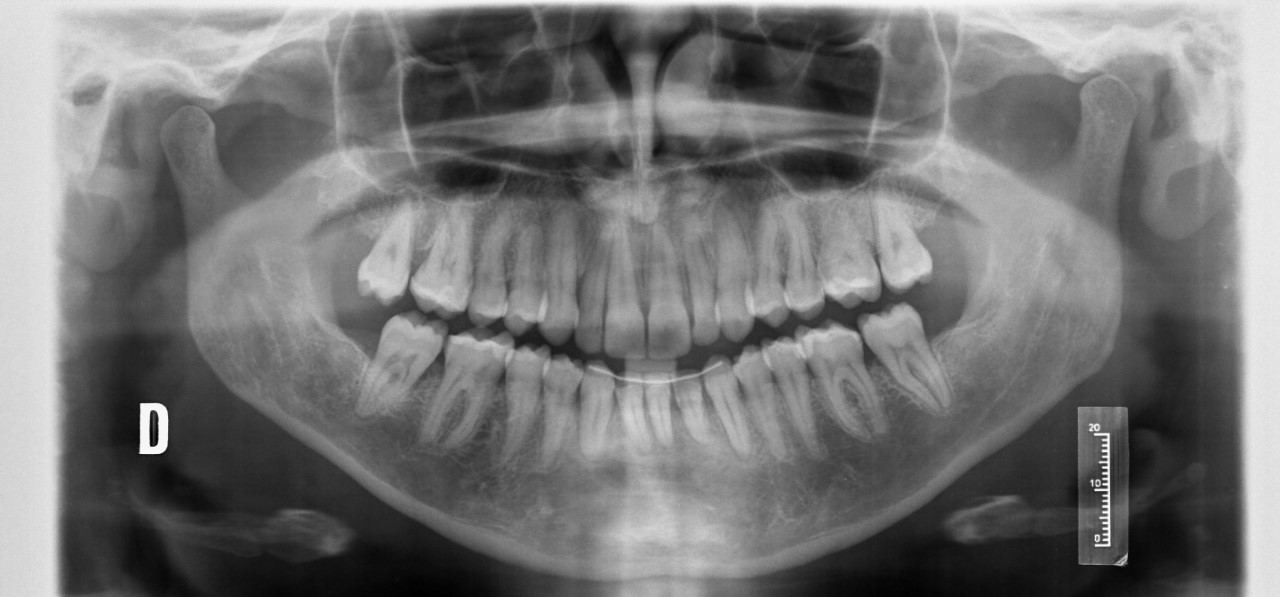

En las imágenes anteriores, mostramos un caso antes y después del tratamiento de ortodoncia. En la primera foto, el paciente presenta todavía su canino temporal. En la segunda foto, ya finalizado el tratamiento, con el canino permanente emplazado en su lugar correcto. La duración de un tratamiento de ortodoncia para traccionar de uno o varios caninos incluidos puede oscilar entre los 20 y los 30 meses.

Radiografías panorámicas: posición de los caninos incluidos antes y después del tratamiento de ortodoncia.